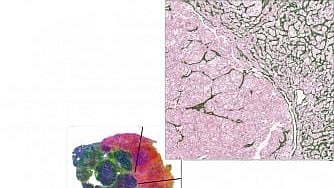

To overcome these challenges, Drs. Kapur and Rajaram and their colleagues at the KCP developed a predictive method using AI to assess histopathological slides – thinly cut tumor tissue sections stained to highlight cellular features. These slides are nearly always part of a patient’s standard workup at diagnosis, and their images are increasingly available in electronic health records, said Dr. Rajaram, also Assistant Professor in the Center for Alzheimer’s and Neurodegenerative Diseases and the Department of Pathology.

Using a type of AI based on deep learning, the researchers “trained” an algorithm using two sets of data: one that matched ccRCC histopathological slides with their corresponding Angioscore, and another that matched slides with a test they developed that assesses blood vessels in the tumor sections.

Importantly, unlike many deep learning algorithms that don’t offer insight into their results, this approach is designed to be visually interpretable. Rather than producing a single number and directly predicting response, it generates a visualization of the predicted blood vessels that correlates tightly with the RNA-based Angioscore. Patients with more blood vessels are more likely to respond to therapy; this approach allows users to understand how the model reached its conclusions.